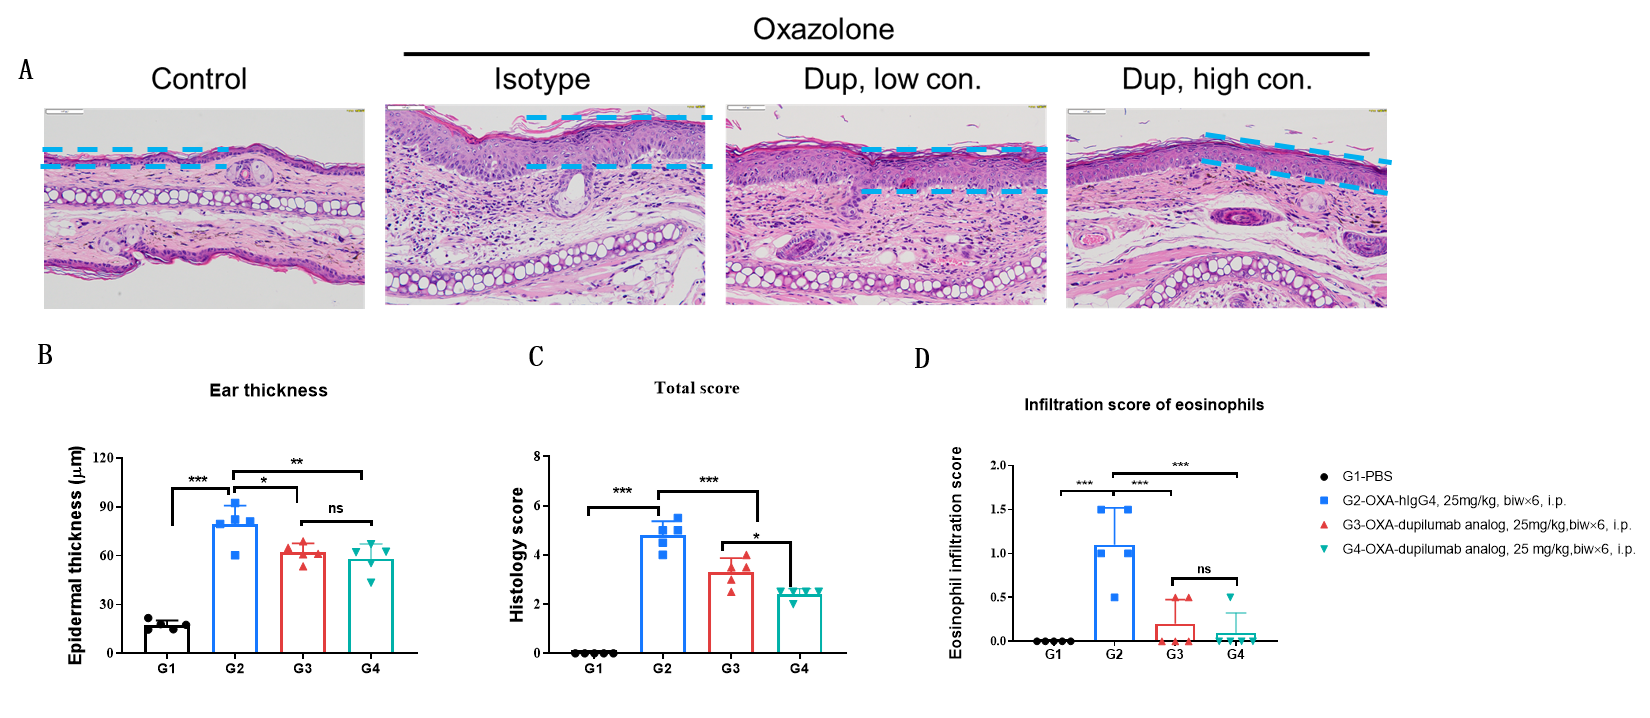

Effects of anti-human IL4RA antibody on inflammatory infiltration in ear skin of the AD mouse model. (A) Hematoxylin and eosin (H&E) staining. (B) Score of eosinophils infiltrated in ear epidermal skin (n=5). Infiltration scores of eosinophils in ear skin were negatively related to the doses of antibody, demonstrating that the B-hIL4/hIL4RA mice provide a powerful preclinical model for in vivo evaluation of anti-human IL4RA antibodies. AD: Atopic dermatitis; ND: Not detectable.

Effects of anti-human IL4RA antibody on inflammatory infiltration in ear skin of the AD mouse model. (A) Hematoxylin and eosin (H&E) staining. (B) Score of eosinophils infiltrated in ear epidermal skin (n=5). Infiltration scores of eosinophils in ear skin were significantly reduced after administration of the antibodies, demonstrating that the B-hIL4/hIL4RA mice provide a powerful preclinical model for in vivo evaluation of anti-human IL4RA antibodies. Infiltration score of eosinophils: 1=slight; 2=mild; 3=moderate; 4=severe. AD: Atopic dermatitis; ND: Not detectable.

Efficacy of anti-human IL4RA antibody in B-hIL4/hIL4RA mice. Dose dependent effects of dupilumab (in house) in oxazolone induced skin lesions in B-hIL4/hIL4RA mice.